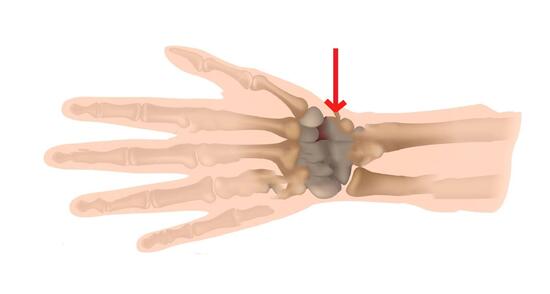

Skafoid kemik tedavisi

Alçı veya atelin süresi uygulanan cerrahi yönteme göre 3 hafta ile 3 ay arasında değişebilmektedir. Bu sürenin sonunda fizik tedavi ve rehabilitasyon uygulamasına geçilir. Amaç el, el bileği ve kolun güç kazanımını sağlamak ve hareket kaybını en aza indirgemektir.

"Kalecimiz Altay Bayındır, dün gerçekleşen antrenmanın şut çalışması sırasında el bileği travması geçirmiştir. Acıbadem Hastanesi'nde yapılan kontrol ve MR sonucunda, kalecimizin el bileği skafoid kemiğinde kırık saptanmış olup ameliyat olmasına karar verilmiştir."

Skafoid kemik tedavisi

Alçı veya atelin süresi uygulanan cerrahi yönteme göre 3 hafta ile 3 ay arasında değişebilmektedir. Bu sürenin sonunda fizik tedavi ve rehabilitasyon uygulamasına geçilir. Amaç el, el bileği ve kolun güç kazanımını sağlamak ve hareket kaybını en aza indirgemektir.

"Kalecimiz Altay Bayındır, dün gerçekleşen antrenmanın şut çalışması sırasında el bileği travması geçirmiştir. Acıbadem Hastanesi'nde yapılan kontrol ve MR sonucunda, kalecimizin el bileği skafoid kemiğinde kırık saptanmış olup ameliyat olmasına karar verilmiştir."